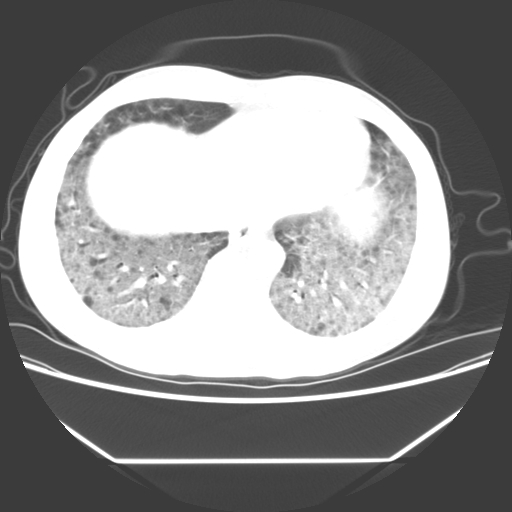

病人55岁,咳嗽,胸闷

忘了传病史了,病人55岁,咳嗽,胸闷

两肺部呈“毛玻璃”状改变,原因待查考虑感染性病变

病人是否发烧,两肺“磨玻璃”影,其间见空气支气管征和碎路石征。考虑肺泡蛋白沉着症。

两肺广泛对称磨玻璃样影,密度不均,考虑机遇性肺部感染。

双肺弥漫磨玻璃样病变,病史很重要。有感冒或发烧史,甲流不除外。无发烧可考虑肺泡蛋白沉积,但肺泡蛋白沉积边缘往往较清晰,与正常肺组织分界清晰

两肺弥漫间质性病变,考虑肺泡蛋白沉着症。建议进一步检查。

两肺“磨玻璃”影,其间见空气支气管征和碎路石征。考虑肺泡蛋白沉着症。

两肺部呈“毛玻璃”状改变,支持肺泡蛋白沉着症。